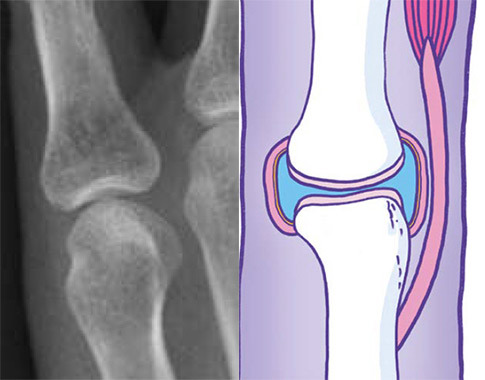

The structures that are shown below represent diagrammatically the changes that occur in the two main types of arthritis. However, it is important to identify those cases where pain may appear to arise from the joint but is in fact referred pain – for example, where the patient describes pain in the left shoulder, which might in fact be referred pain from the diaphragm, the neck, or perhaps ischaemic cardiac pain. In cases where examination reveals no abnormalities in the joint, other clues will be obtained by taking a thorough history. A common cause of widespread pain with normal joint examination for example is fibromyalgia.

X-ray and cross-sectional diagram of a synovial joint and it’s periarticular structures